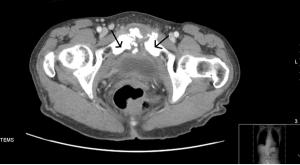

Presenting complaints were fever, nausea, and lower abdominal pain that worsened with walking. Osteomyelitis is not commonly included in a differential for abdominal pain. This case is different.